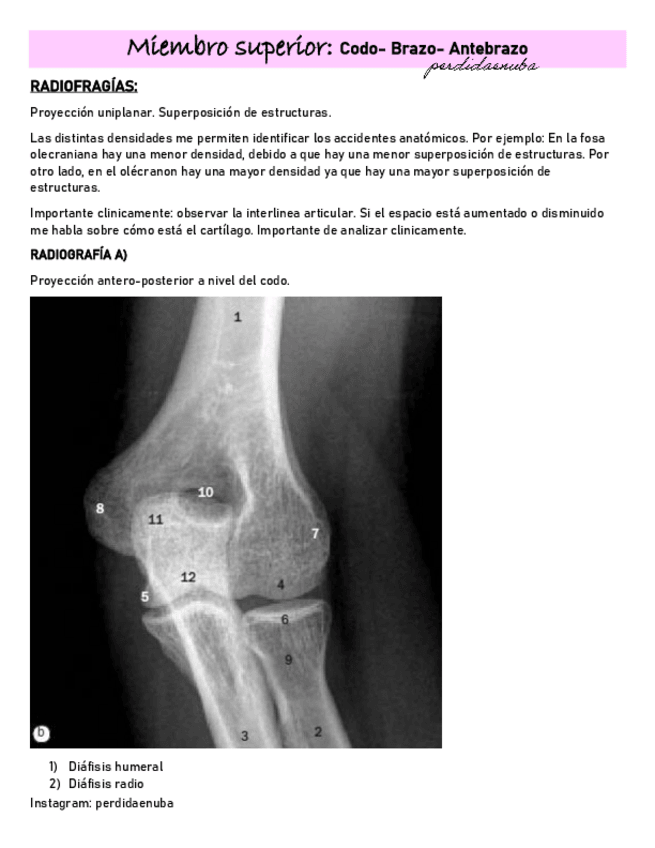

He publicado nuevos apuntes de 8º Cirugía General: BRAZO-CODO-ANTEBRAZO-.pdf